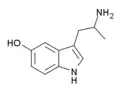

List of substituted α-alkyltryptamines

α-Alkyltryptamines are a group of substituted tryptamines which possess an alkyl group, such as a methyl or ethyl group, attached at the alpha carbon, and in most cases no substitution on the amine nitrogen.[17][18][19] α-Alkylation of tryptamine makes it much more metabolically stable and resistant to degradation by monoamine oxidase, resulting in increased potency and greatly lengthened half-life.[19] This is analogous to α-methylation of phenethylamine into amphetamine.[19]

5-HO-αMT (αMS/α-methyl-5-HT) | 3-(2-aminopropyl)-1H-indol-5-ol | 304-52-9 |